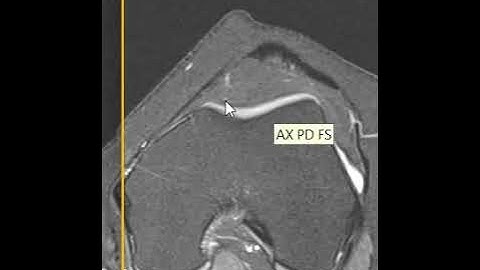

Patellar Instability - What and How to Measure